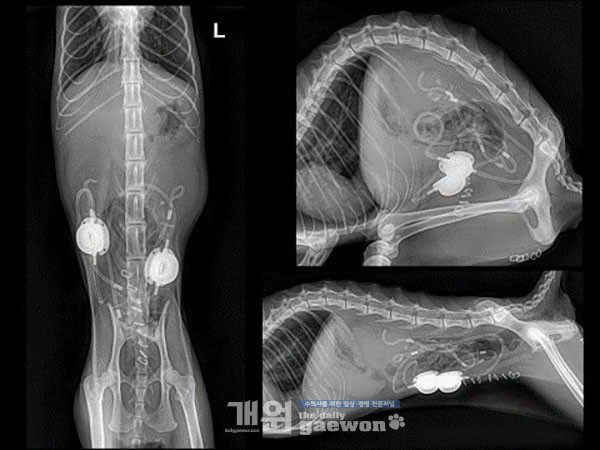

복부 영상에서 Peritoneal contrast는 정상적으로 관찰됩니다. 간 음영은 비교적 작게 관찰 됩니다. 좌측 신장 음영의 위치로 최대 2.9x2mm 크기의 mineral opacity 음영이 다수 관찰됩니다.

Lateral view에서 L4-5 level의 retroperitoneal space, VD view에서 L3 level의 좌측 proximal ureter, L5 level의 midline 양측으로 mineral opacity 음영이 다수 관찰됩니다.

좌측 신장 음영은 L2 길이의 2.3배 정도로 정상 범위 내 size로 관찰됩니다. 우측 신장 음영은 L2 길이의 3배 정도로 크고, irregular margin으로 관찰됩니다.

Lt. renal calculi가 진단되고, 감별진단으로서 Enlarged right kidney: hydronephrosis, Mineral opacity materials in retroperitoneal space: ureteral calculi(left-non/partial obstructive, right-obstructive)가 있습니다(그림 5).